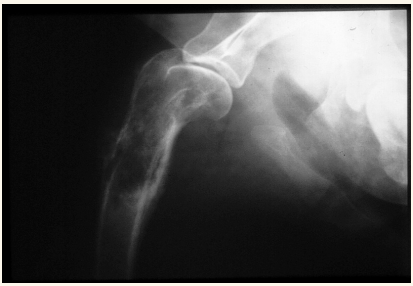

Hombro:

Luxaciones lo mas común (Puede ser congénita y traumática). Puede haber Osteocondritis disecante, Fracturas o EDA (Enfermedad Degenerativa Articular)

Luxación Coxo-femoral

- Por traumatismo, a veces leve si existe Displasia. Suele aparecer con fracturas de pelvis, uni o bilateral

- Normalmente cráneo-dorsal, aunque puede ser dorsal, ventral, caudal (rara) o intrapélvica

- Mejor 2 proyecciones pero en VD se ve mejor (ilion desplazado, mayor tamaño articular, perdida de contorno liso)

- Hay que ver la direccion de la luxacion. La mas frecuente es craneo-dorsal pero hay mas.